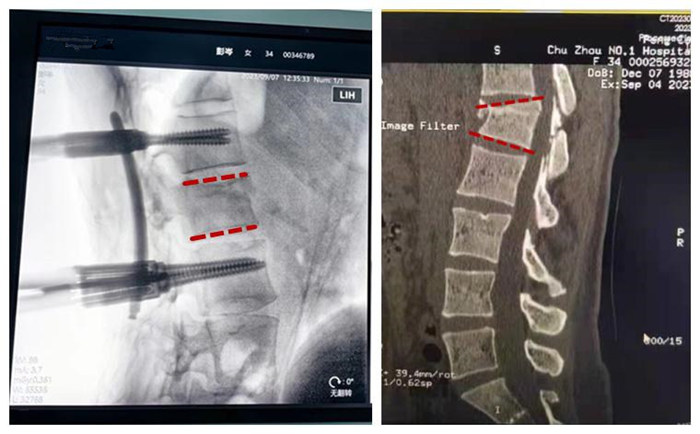

术中机器人对腰椎置钉路线进行精准规划

手术医师在机器人三维影像智能引导下,操作机械臂通过微创的方式,在脊柱上“打钉子”,使手术切口更小、损伤更小、出血更少、术后康复更快。术后影像显示,钉钉子的大小、位置、角度都接近完美。

术中透视见骨折复位完美,螺钉位置满意

术后与术前椎体高度及后凸矫正对比,疗效显著